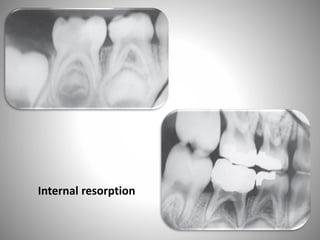

• 1- INTERNAL RESORPTION:

• Radiographic evidence of internal resorption occurring within the

pulp canal several months after the pulpotomy procedure is the

most frequently seen evidence of an abnormal response in primary

teeth. Internal resorption is a destructive process generally believed

to be caused by odontoclastic activity, and it may progress slowly or

rapidly. Occasionally, secondary repair of the resorbed dentinal area

occurs.

• No satisfactory explanation for the post-pulpotomy type of internal

resorption has been given. It has been demonstrated, however, that

with a true carious exposure of the pulp, an inflammatory process

of some degree will be present. The inflammation may be limited to

the exposure site, or it may be diffuse throughout the coronal

portion of the pulp. Amputation of all the pulp that shows the

inflammatory change may be difficult or impossible, and abnormal

pulp tissue may be allowed to remain

Internal resorption